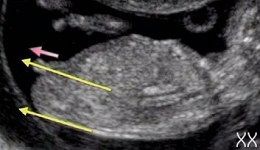

ничего там не видно, у мальчиков и девочек на этом сроке все одинаково — пиписьки =) и ракурс совсем не тот что бы что-то выглядеть, это просто фото так сказать вам на память) Я в 13 недель делала, врач сказала, что пол можно узнать будет на втором УЗИ, сейчас никаких гарантий. Аппарат кстати хороший и смотрели вагинально. Предположить можно что угодно, а на деле результат на таком сроке 50/50Вот вам про бугорки http://www.budumamoi.ru/uzi_development.html

Если бы Вы посмотрели чуть ниже обсуждение, то заметили бы, что я уже показывала фото именно с этого сайта про бугорки :) Что все очень видно и понятноУ меня 4 беременность и хороший специалист последние три беременности безошибочно (!!!!) говорил пол на сроке 12 недель. Так что спорить не буду. У меня своя статистика :)

Ир, я написала, где мальчишеский бугорок видно, у девочек по другому он идет.